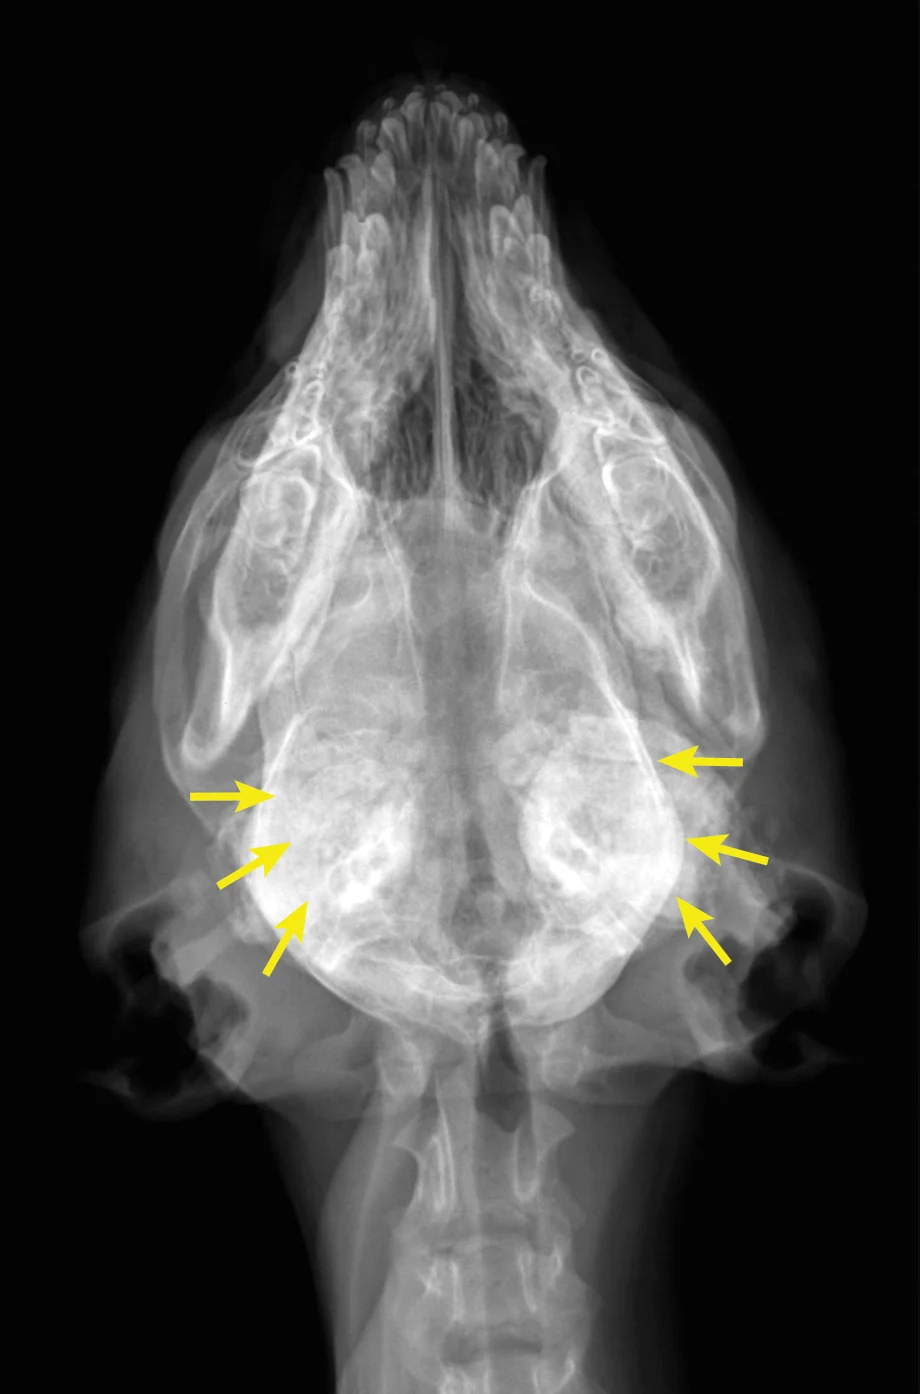

Diagnosis is based on signalment, history, clinical signs, and radiographic findings. Although biopsy and histopathology can help confirm diagnosis, they are typically not necessary, as radiographic findings are often pathognomonic (Figure 1). However, although standard radiographs can confirm diagnosis, CT may be helpful in assessing if the temporomandibular joints are affected.

(A) Lateral and (B) ventrodorsal radiographs of the skull. This patient was diagnosed with calvarial hyperostosis. Note that the frontal, parietal, and occipital bones, including the tentorium osseum, are smooth but have increased thickness and opacity (red arrows). Note the markedly irregular periosteal reactions on the mandibles and bullae (yellow arrows). This patient was unable to open its mouth much beyond what is evident on the lateral image. Images courtesy of Justin Goggin, DVM, DACVR